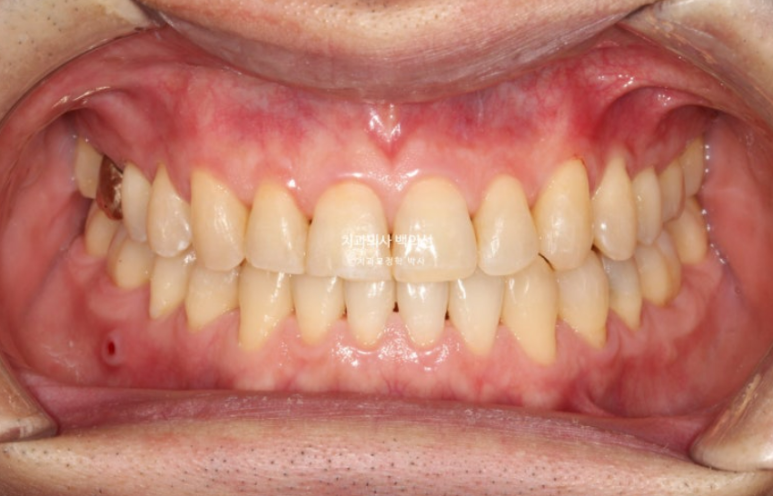

25년 3월까지 4개월동안 추가장치를 모두 낀 후 치료를 마무리 했습니다.

25.03

중심선은 잘 맞아졌습니다.

어금니 교합은 좋고

유지장치까지 붙은 모습입니다.

처음에 예상 치료기간은 1년 반 설명드렸으나 치료가 1년 3개월만에 잘 마무리가 되었습니다.